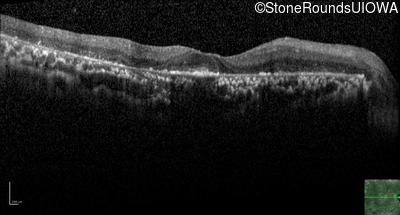

AR Retinitis Pigmentosa (IA1aiii)

Age at visit: 43 years

This 43 year old woman has had poor peripheral vision and poor night vision since childhood. She recalls sometimes having to back-up to find something she dropped on the floor. She first came to ophthalmologic attention at age 10 when there was concern for cataract formation associated with high doses of oral steroids she was receiving for asthma.